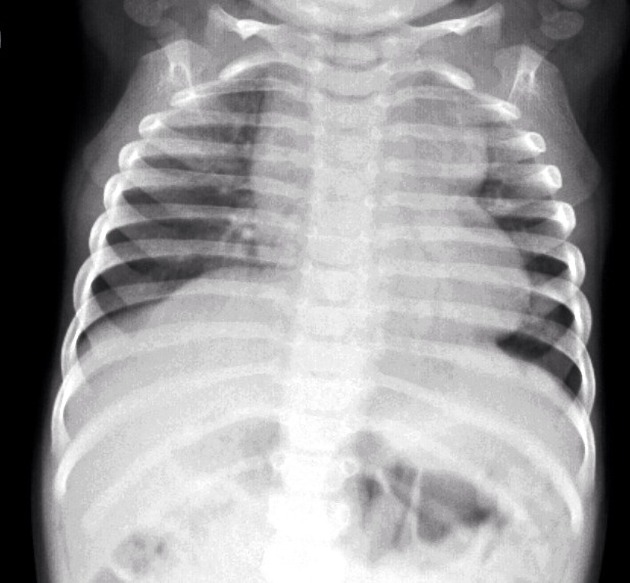

1. Imaging in Cyanotic Congenital Heart Disease By Dr. Resham Singh Thakur

Dr. Resham Singh Thakur delivers a comprehensive session on imaging in cyanotic congenital heart diseases, with a sharp focus on what radiology residents and clinicians need to know for real-world applications.

• Differentiating cyanotic and acyanotic CHDs through imaging

• Key conditions like Tetralogy of Fallot and Tricuspid Atresia

• Exam tips and clinical insights for reporting CHDs effectively

Perfect For: Radiology & Pediatric Cardiology PGs, residents preparing for exams, and clinicians in CHD diagnosis.